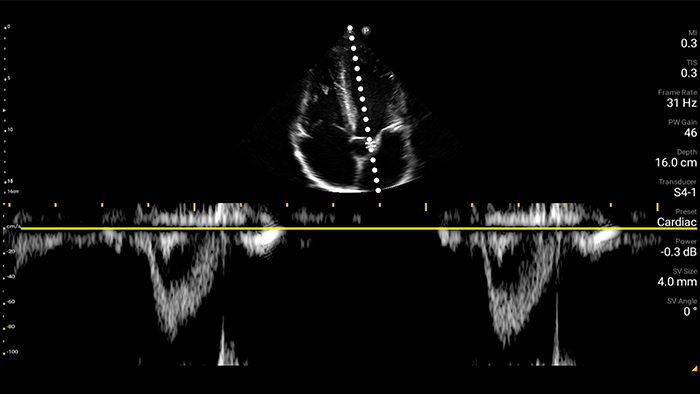

Exceptional ultrasound imaging

Lumify handheld ultrasound offers images that enhance diagnostic confidence.